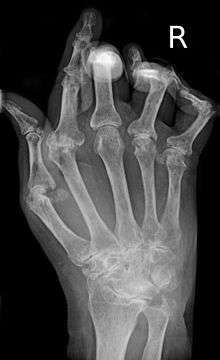

A hand affected by rheumatoid arthritis | |

While the cause of rheumatoid arthritis is not clear, it is believed to involve a combination of genetic and environmental factors. The underlying mechanism involves the body's immune system attacking the joints. This results in inflammation and thickening of the joint capsule. It also affects the underlying bone and cartilage.[1] The diagnosis is made mostly on the basis of a person's signs and symptoms.[2] X-rays and laboratory testing may support a diagnosis or exclude other diseases with similar symptoms.[1] Other diseases that may present similarly include systemic lupus erythematosus, psoriatic arthritis, and fibromyalgia among others.[2]

As the pathology progresses the inflammatory activity leads to tendon tethering and erosion and destruction of the joint surface, which impairs range of movement and leads to deformity. The fingers may suffer from almost any deformity depending on which joints are most involved. Specific deformities, which also occur in osteoarthritis, include ulnar deviation, boutonniere deformity (also "buttonhole deformity", flexion of proximal interphalangeal joint and extension of distal interphalangeal joint), swan neck deformity (hyperextension at proximal interphalangeal joint and flexion at distal interphalangeal joint) and "Z-thumb." "Z-thumb" or "Z-deformity" consists of hyperextension of the interphalangeal joint, fixed flexion and subluxation of the metacarpophalangeal joint and gives a "Z" appearance to the thumb.[11]:1089 The hammer toe deformity may be seen. In the worst case, joints are known as arthritis mutilans due to the mutilating nature of the deformities.[14] "Spindling of fingers" of hand occurs due to swelling of the PIP but not DIP joints. "Piano key movement" of the ulnar styloid occurs due to inflammation around the ulnar styloid and tenosynovitis of extensor carpi ulnaris.

X-rays of the hands and feet are generally performed in people with many joints affected. In RA, there may be no changes in the early stages of the disease or the x-ray may demonstrate juxta-articular osteopenia, soft tissue swelling, and loss of joint space. As the disease advances, there may be bony erosions and subluxation. X-rays of other joints may be taken if symptoms of pain or swelling occur in those joints.